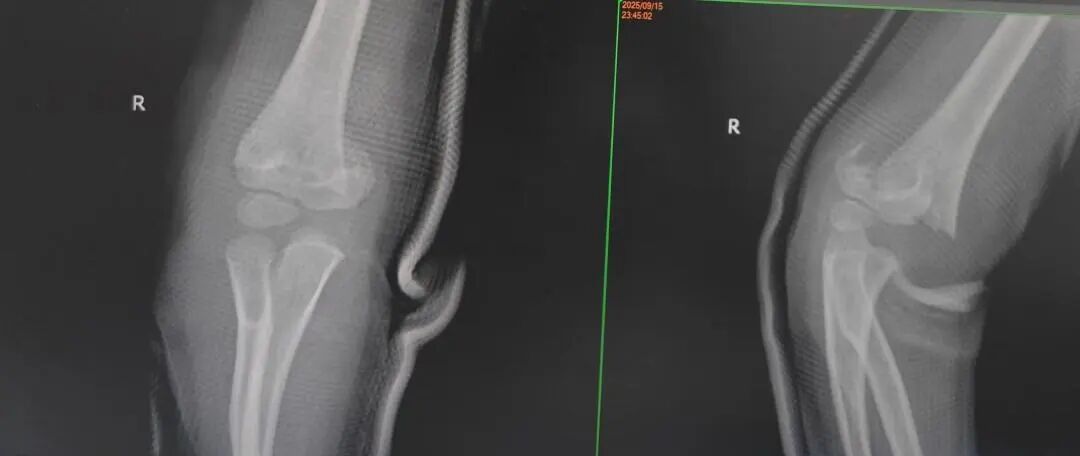

4岁的小罗:9月15日,在家追跑玩耍时撞到桌角,右侧肱骨髁上骨折;

7岁的小周:9月15日,在家爬沙发时摔落,左肱骨外髁骨折;

10岁的小唐:9月18日,在学校操场奔跑时摔倒,左肱骨髁上骨折……